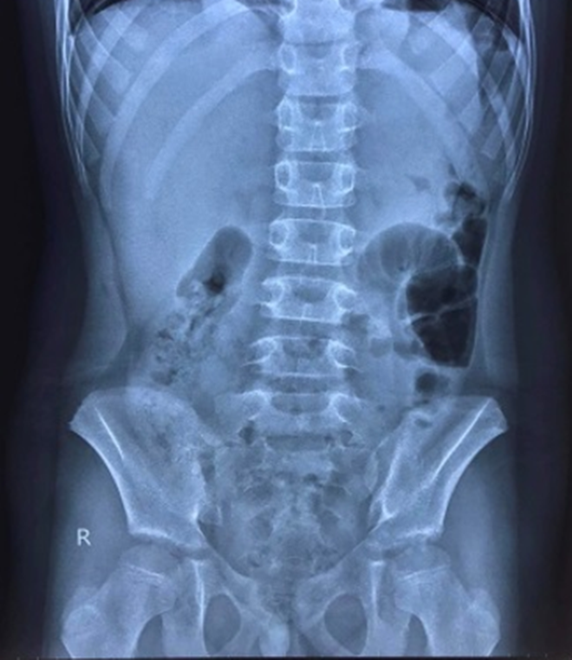

Trường hợp đầu tiên là bệnh nhi 10 tuổi, được Bệnh viện Trẻ em Hải Phòng hội chẩn từ xa với Trung tâm y tế huyện Tiên Lãng, cuối tháng 2. Trẻ mắc Covid-19 kèm đau bụng dữ dội vùng trên rốn, sốt, nôn, chụp X-Quang nghi ngờ thủng tạng rỗng. Nhận thấy đây là trường hợp cấp cứu ngoại khoa cần xử trí kịp thời nên bệnh viện chỉ đạo chuyển bệnh nhân lên Bệnh viện Trẻ em Hải Phòng để điều trị.

Tại Khoa truyền nhiễm, các bác sĩ chẩn đoán trẻ bị viêm phúc mạc do thủng dạ dày. Bệnh nhi được cấp cứu phẫu thuật nội soi khâu lỗ thủng dạ dày, làm sạch, dẫn lưu ổ bụng.

Bệnh viện sau đó xử trí thêm một bệnh nhi khác mắc Covid-19, vào viện với triệu chứng đau bụng dữ dội vùng trên rốn kèm nôn. Bác sĩ chẩn đoán thủng dạ dày, xứ trí cấp cứu. Hiện, các bé đã bình phục và xuất viện.